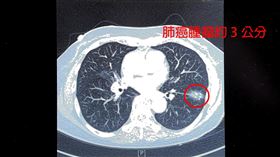

7旬婦不菸酒罹肺癌 竟和「1病」有關係

新竹一名75歲婦人不菸不酒,但在健檢時發現左下肺葉有...

2025/09/15 10:52